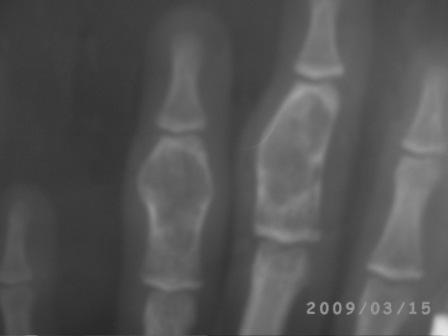

Уважаемые коллеги! Обратилась девочка 15 лет с жалобами на боли, отечности 4-го пальца кисти.

Заметила утолшение среднего фаланга 3 и 4-го пальцев 3,5-4 года назад, последний год начала чувствовать периодические боли, особенно в холодное дни, когда долго писала и всё. 4 дня назад получила легкий ожог пламенем кисти и пальцев, а 2 дня назад ударилась о волейбольный мяч и после этого в 4-м пальце нарастал отек , появилась резкая болезненность, усиливаюшийся при движении и пальпации, умеренная местная температура, а в 3-м пальце имеется утолшение среднего фаланга, следи ожога, безболезненный, отек м/тканей и местной температурй нет. Мы предполагаем ОБК, похоже и на фиброзную дисплазию, и краевой перелом сред. фаланга 4-го пальца и поэтому такая картина!

По рентгенограмме на ОБК не похоже.

Это энхондрома.

Стояние довольно приличное. Хорошо, что сохранили суставы. В такой ситуации вообще-то ничего и не придумаешь, кроме спиц. Поэтому я бы не менял метода фиксации. По снимкам больше похоже было на энхондрому, но вот меня смущает белесоватый цвет содержимого и кашицеобразная консистенция. Подождем гистологии.

А это и есть болезнь Олье! Как есть - классика. Она же - "энхондрома". Требует тщательного выскабливания и адекватного замещения. Хронос, аутокость - очень подходит. Не переживайте из-за тонких стенок, отбросьте эмоции по поводу "папиросной бумаги". Всё будет хорошо. Главное - спицы не забыть удалить вовремя. Болячка эта любит детей из близко родственных браков в изолированно живущих популяциях людей.